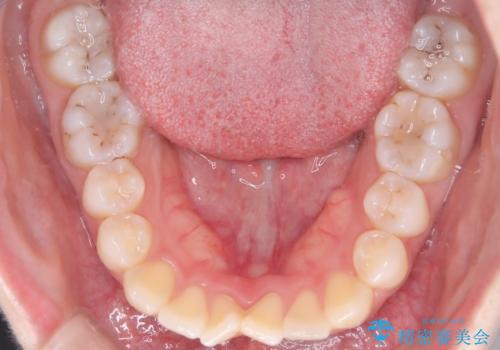

【ワイヤー矯正】前歯の突出感、下の歯の並びを良くしたい

- 主訴:上の前歯の突出感と下の歯の並びを改善したい

非抜歯で矯正治療を行った場合と、上下左右4番目の歯を抜歯して矯正治療を行った場合のシミュレーションを見ていただき、非抜歯での矯正治療を希望されました。

非抜歯にて矯正治療を行いました。

IPRを行い、前歯部の突出感の改善に努めました。

期間:1年9カ月